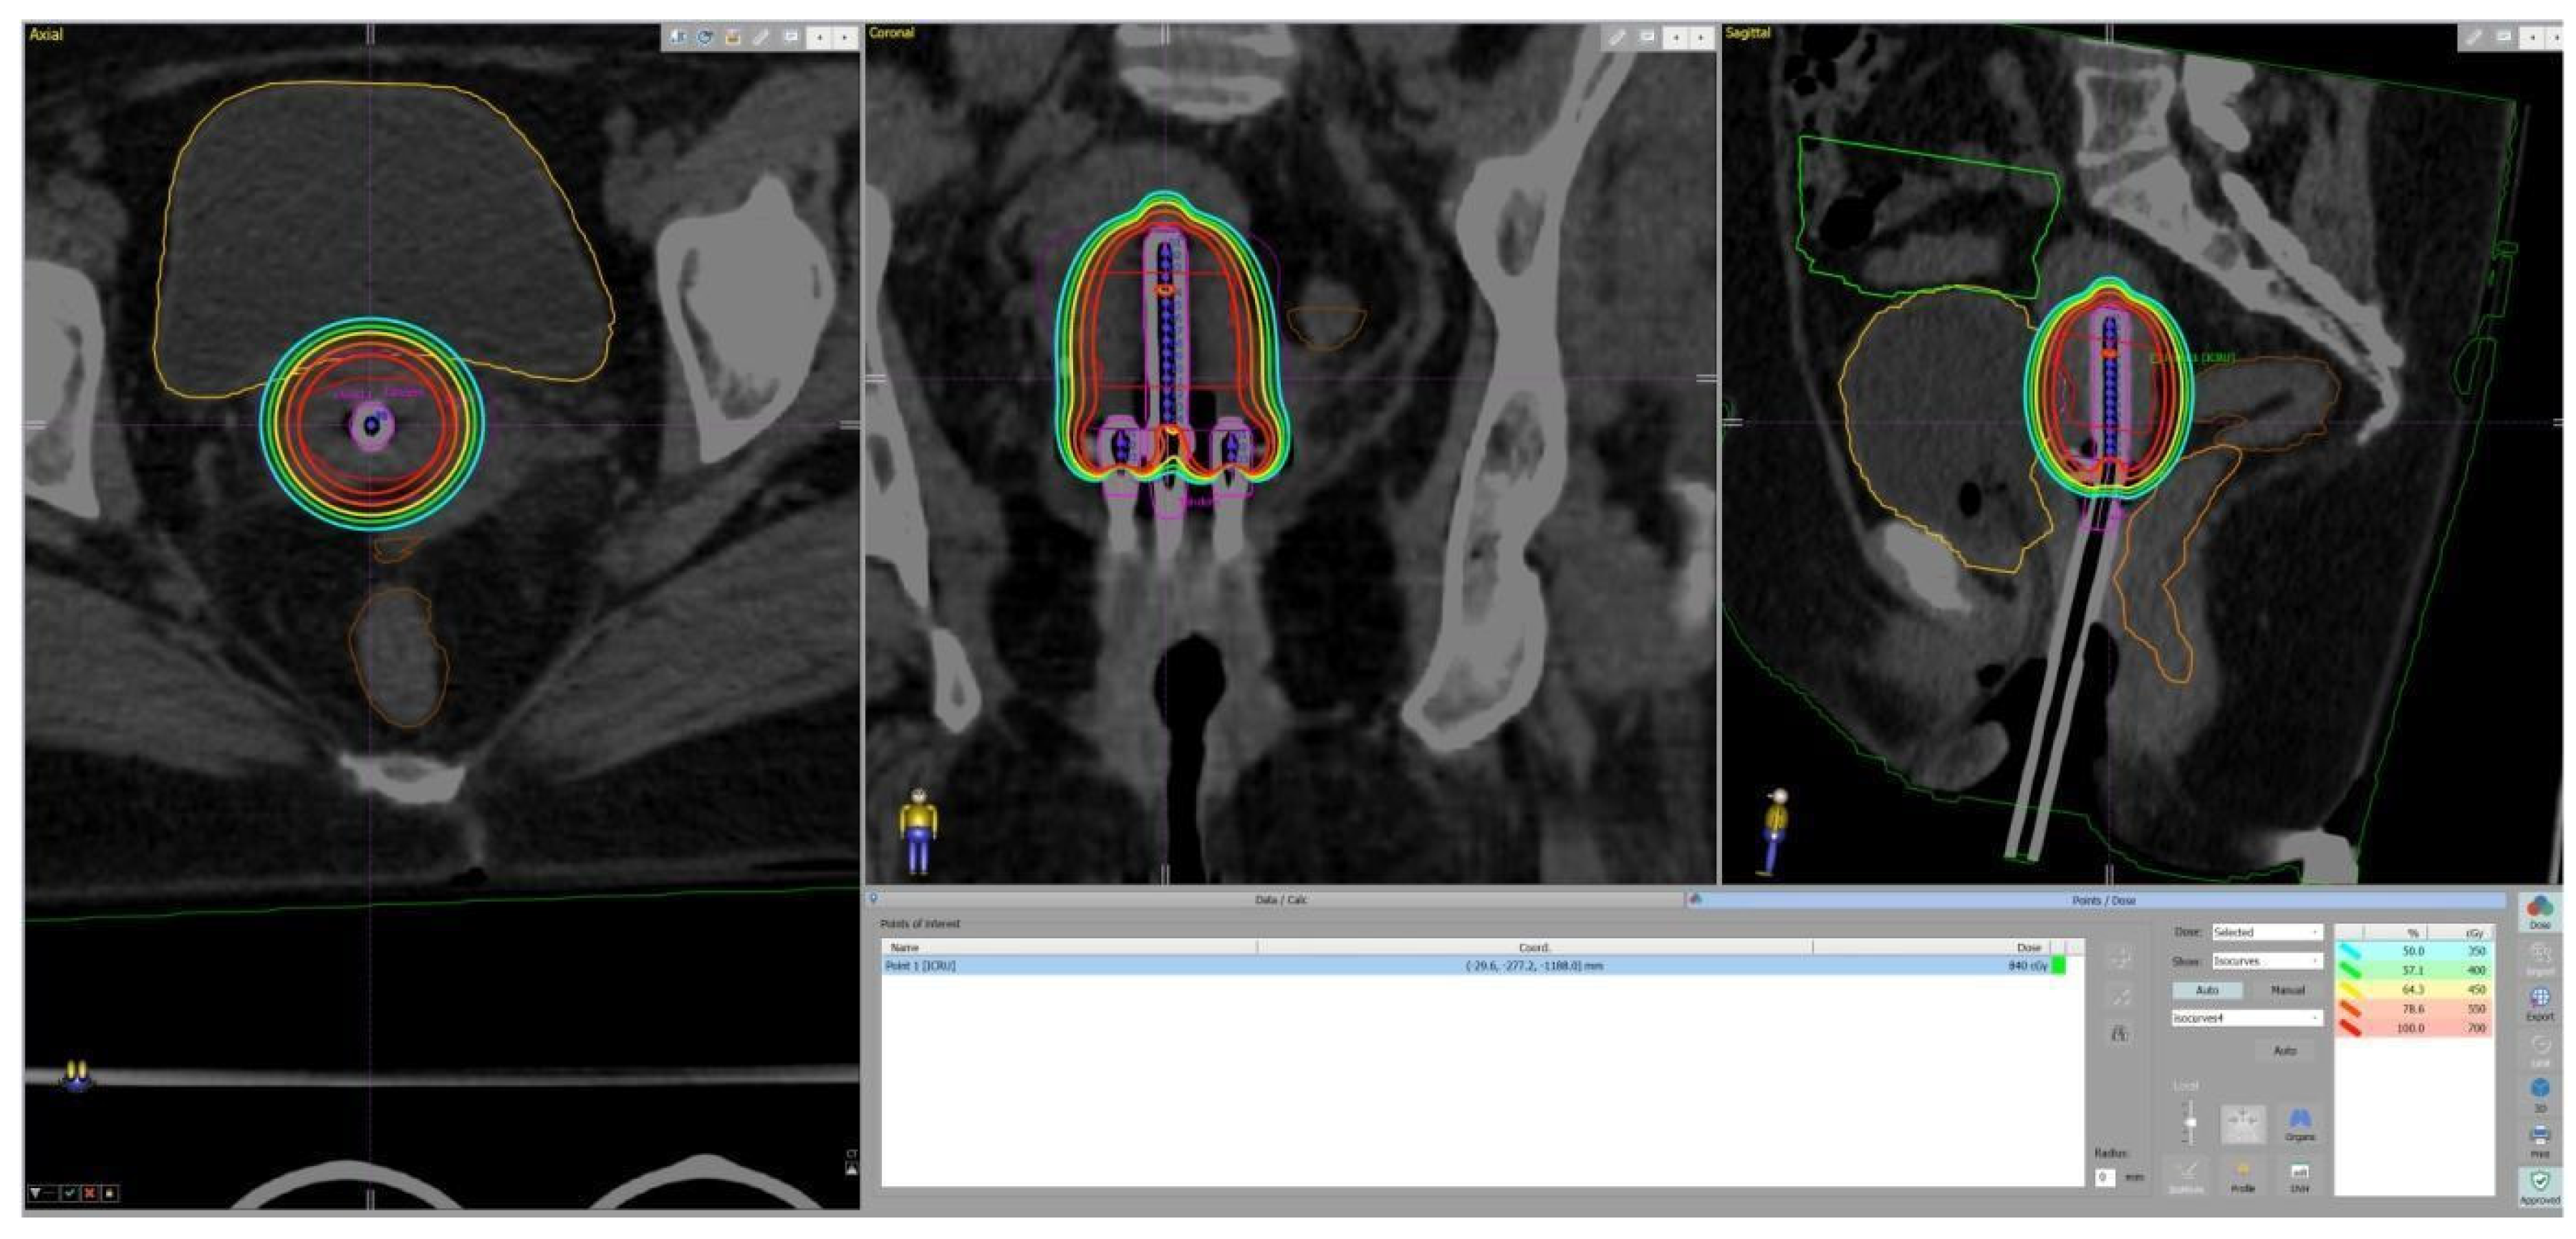

2. Materials and Methods